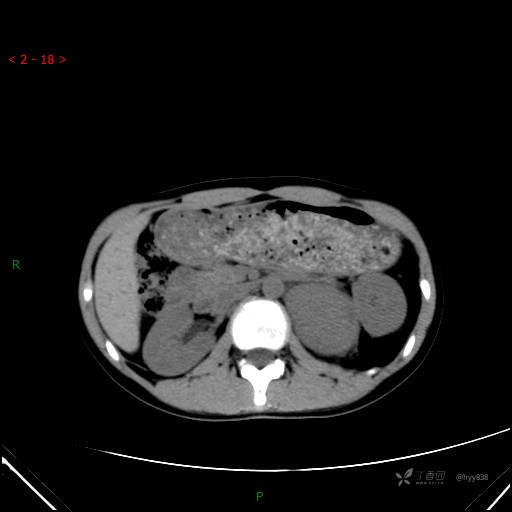

增强静脉期